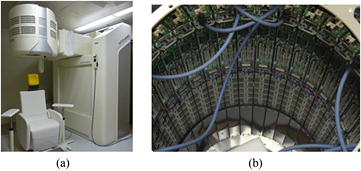

The detector ring consists of 32 DOI detector modules arranged in a shape with a 430 mm diameter and 168 detector rings with a 1.2 mm pitch. The 168 detector rings include the number of gaps equivalent to eight crystal segments, where there is a gap of 2.4 mm, equivalent to two crystal segments, between crystal arrays. The total number of crystals is 655 360. The transaxial FOV is 330 mm in diameter and the axial FOV is 201.6 mm, which are sufficient to cover a whole human brain. The major characteristics of the Hamamatsu brain PET scanner are listed in table 1. The gantry head, including the DOI detector modules, has a compact cylindrical shape with outer dimensions of approximately 740 mm in diameter and 770 mm in height. The detector head is able to move up and down, as well as forward and backward, and to tilt. Thus, the patient can take various positions, such as sitting, lying, and standing. Photographs of the gantry and the inner detector ring are shown in figure 3.

Figure 3. Photographs of (a) the gantry and (b) the inner detector ring.